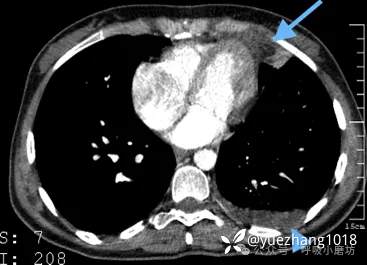

54岁女性患者,表现为突发胸膜炎样胸痛,初次发作后2天自行缓解。心电图和胸部X光都正常。3周后疼痛复发。

第二次就诊时胸片显示左心缘旁明确高密度影(图2A)。CT显示病灶为脂肪密度(CT值-48 HU),边缘见环状强化(图2B),并伴有邻近心包膜局限性增厚。

图2A 胸部X线片显示左心旁高密度影(箭头所示);2B 增强CT显示心旁高密度影对应被厚环包绕的心包外脂肪(箭头所示),注意伴随的心包增厚(箭)

予镇痛对症处理后患者疼痛于1周内消失。

2个月后影像学随访证实心旁密度消失(图2C)。胸部CT显示脂肪病变及邻近心包增厚显著减小(图2D)。

图2C 2个月获得的随访胸部X线片显示心旁高密度影已消失;2D 随访CT显示心包外病灶体积显著缩小(箭头所示),相邻心包增厚已消失